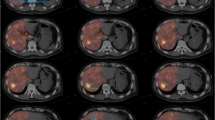

Agreement of intrahepatic distribution was also measured quantitatively. FDG-PET/CT pre-treatment scans were used for segmentation of lesion and liver volumes (volumes of interest, or VOIs). In-house-developed software was used for this purpose (VolumeTool, version 1.6.5.) [13]. Delineation of VOIs was performed manually on FDG-PET images. The normal liver was defined as the whole liver minus tumors. All VOIs were manually registered (non-deformable) to the 99mTc-MAA SPECT, 166Ho-scout SPECT, and 166Ho-therapeutic dose SPECT images (Fig. 1). In order to compensate for co-registration errors and blurring effects, the VOIs were enlarged by a 1-cm margin when measuring the activity. Also, small lesion VOIs with a volume smaller than 10 mL were excluded, because of their higher sensitivity to these errors. The pre-treatment 99mTc-MAA SPECT and 166Ho-scout SPECT and the post-treatment 166Ho-therapeutic dose SPECT were converted into units of 166Ho-activity concentration by normalization of the total number of reconstructed counts to the total administered activity of 166Ho during therapy. This resulted in two predictive amounts of 166Ho (MBq/cm3) for each VOI, based on both pre-treatment SPECT images, in comparison with an actual amount of 166Ho based on post-treatment SPECT. The lesion-absorbed dose was calculated by dividing the activity measured in the lesion VOI plus the 1-cm margin by the volume of that same lesion VOI without the 1-cm margin. Normal liver activity was calculated by subtraction of the measured activity of all lesion VOIs within one patient (including the VOI’s with a volume smaller than 10 mL) without 1-cm margin from the activity of the liver VOI with 1-cm margin. The volume of the normal liver compartment was calculated by subtraction of the total volume of the lesion VOIs without margin from the volume of the liver without margin. Finally, the calculated activity was divided by this volume to calculate the normal liver absorbed dose. No extrahepatic activity distribution and no interval change in liver morphology were assumed. Contribution of gamma radiation was neglected in calculating the absorbed dose. To illustrate clinical implications, the calculated activity concentrations were converted into units of Gray for both the lesion and normal liver segmentations, using a conversion factor of 15.78 ∙ 10−3 Gy/(MBq/kg) assuming a liver density of 1.06 kg/L [10].

Example of discrepancy between 99mTc-MAA and 166Ho-therapeutic dose. Despite identical catheter positions (upper row), there is a remarkable difference in activity distribution between the three procedures. SPECT-CT (middle and lower row) shows that the activity distribution in the liver of 166Ho-scout is more similar to the therapy distribution than 99mTc-MAA. Overall agreement of 99mTc-MAA was rated 2.5 compared to 4.5 for 166Ho scout for this patient